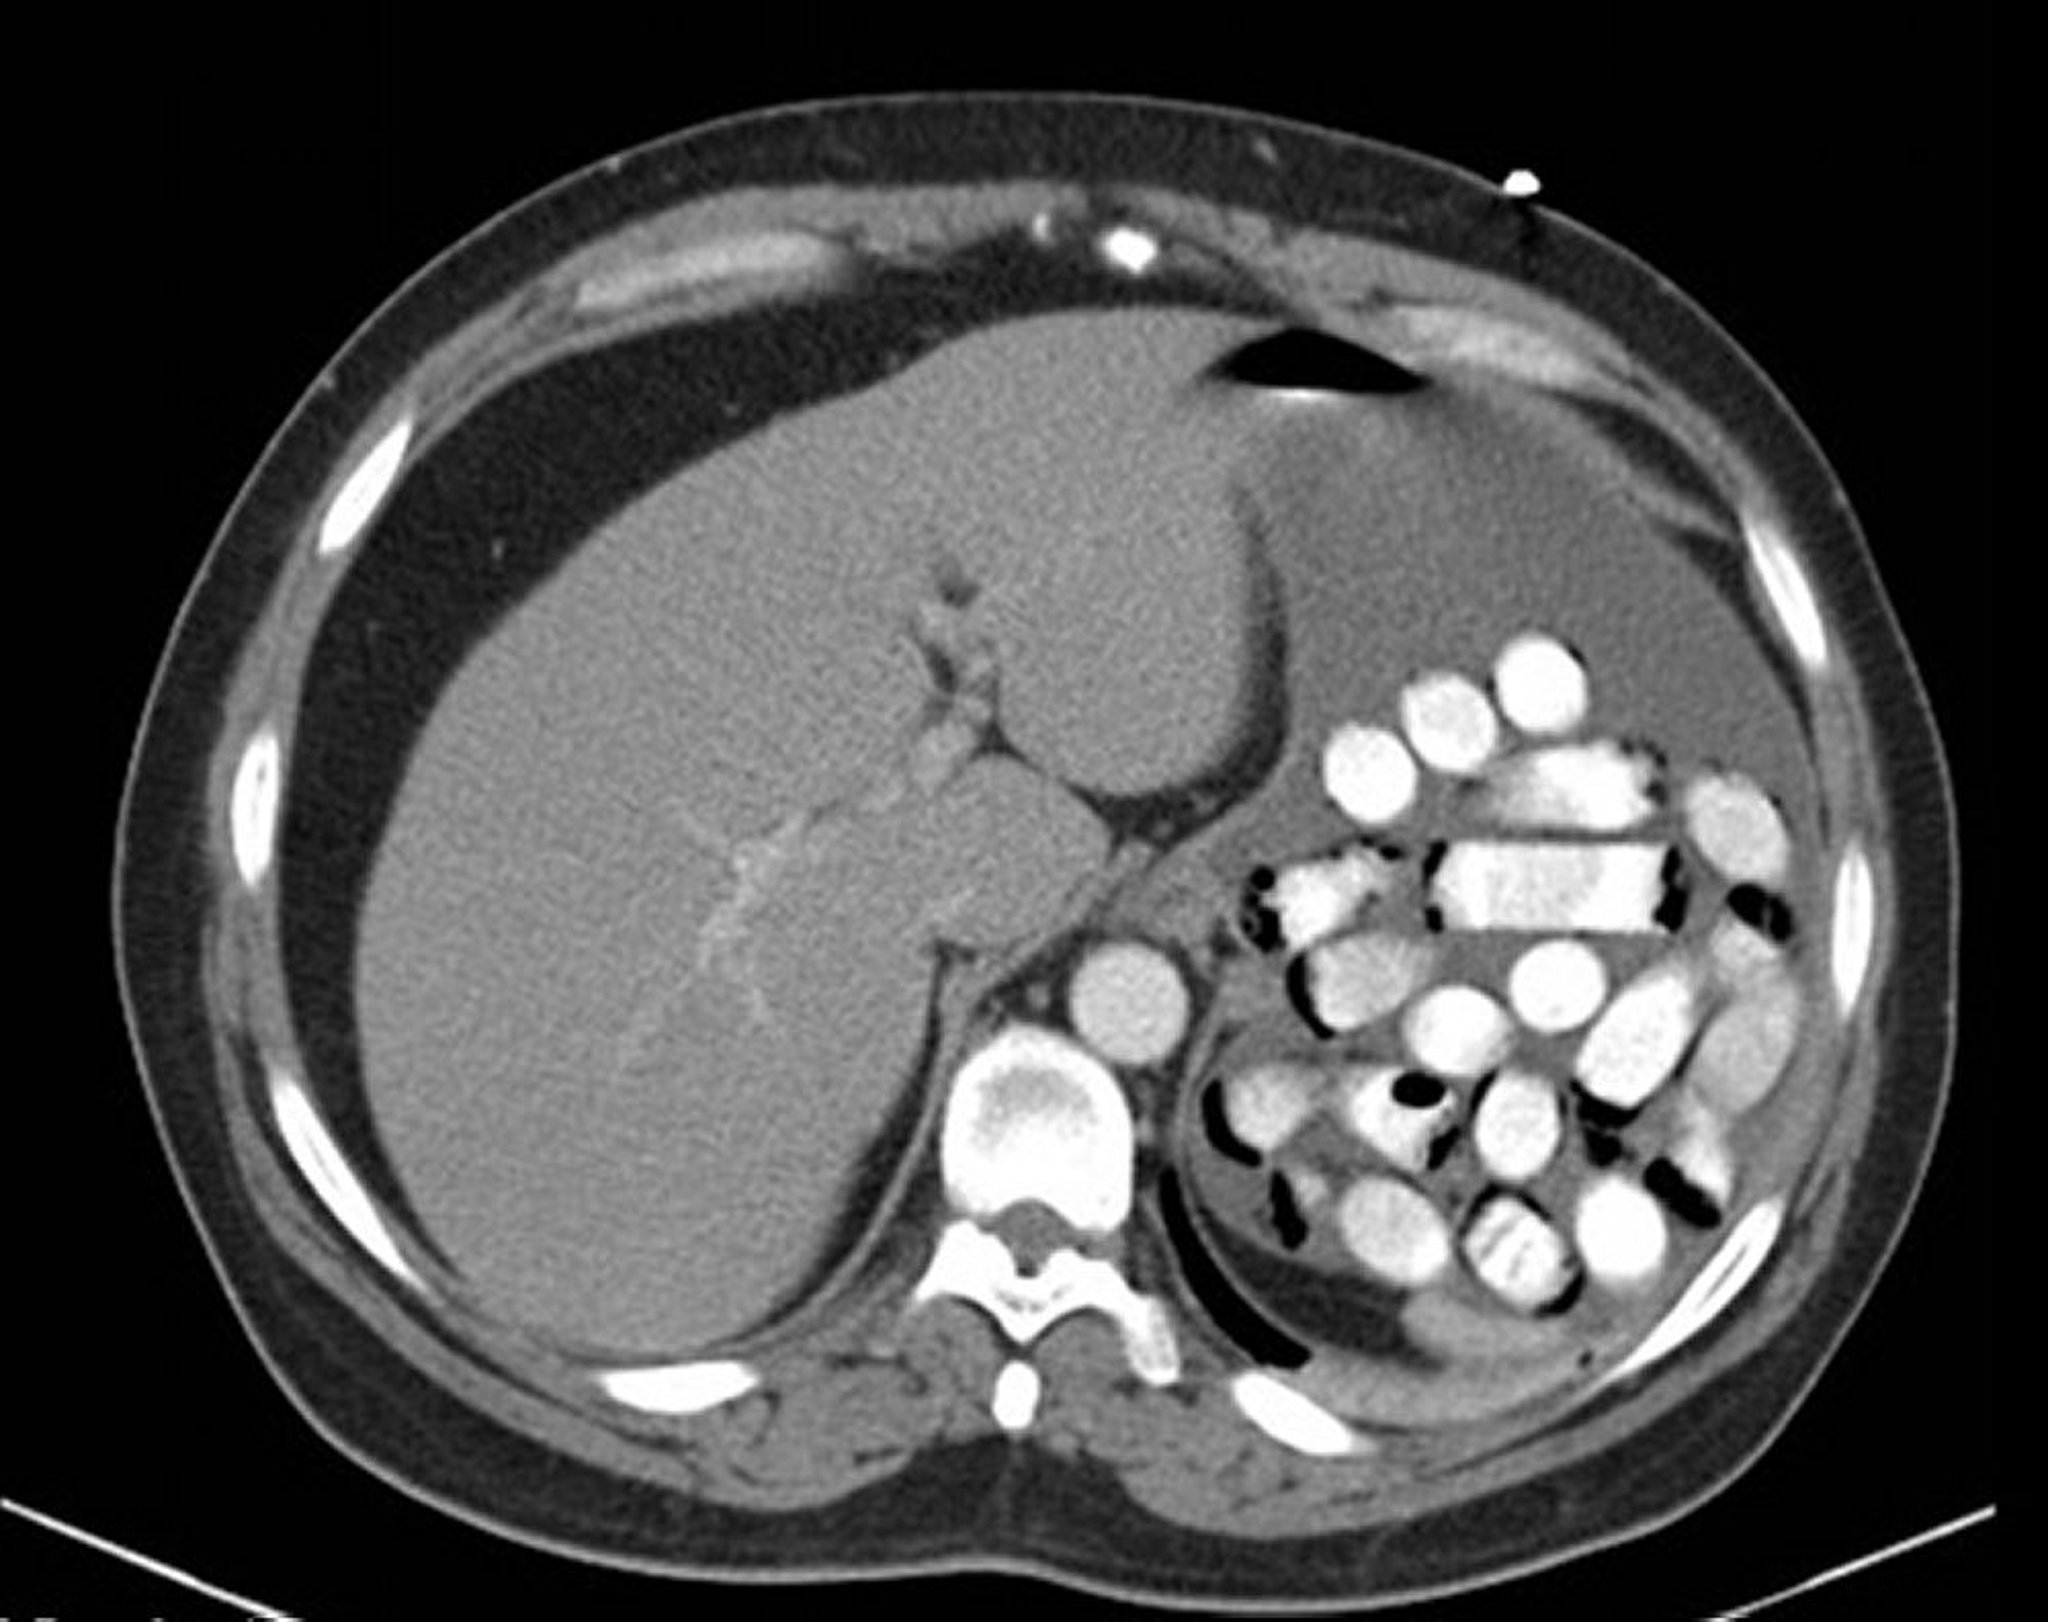

Инородные тела желудка (КТ)

Это изображение показывает пакетики с наркотическими веществами в желудке.

Изображение предоставлено врачом-остеопатом Alan Gingold.